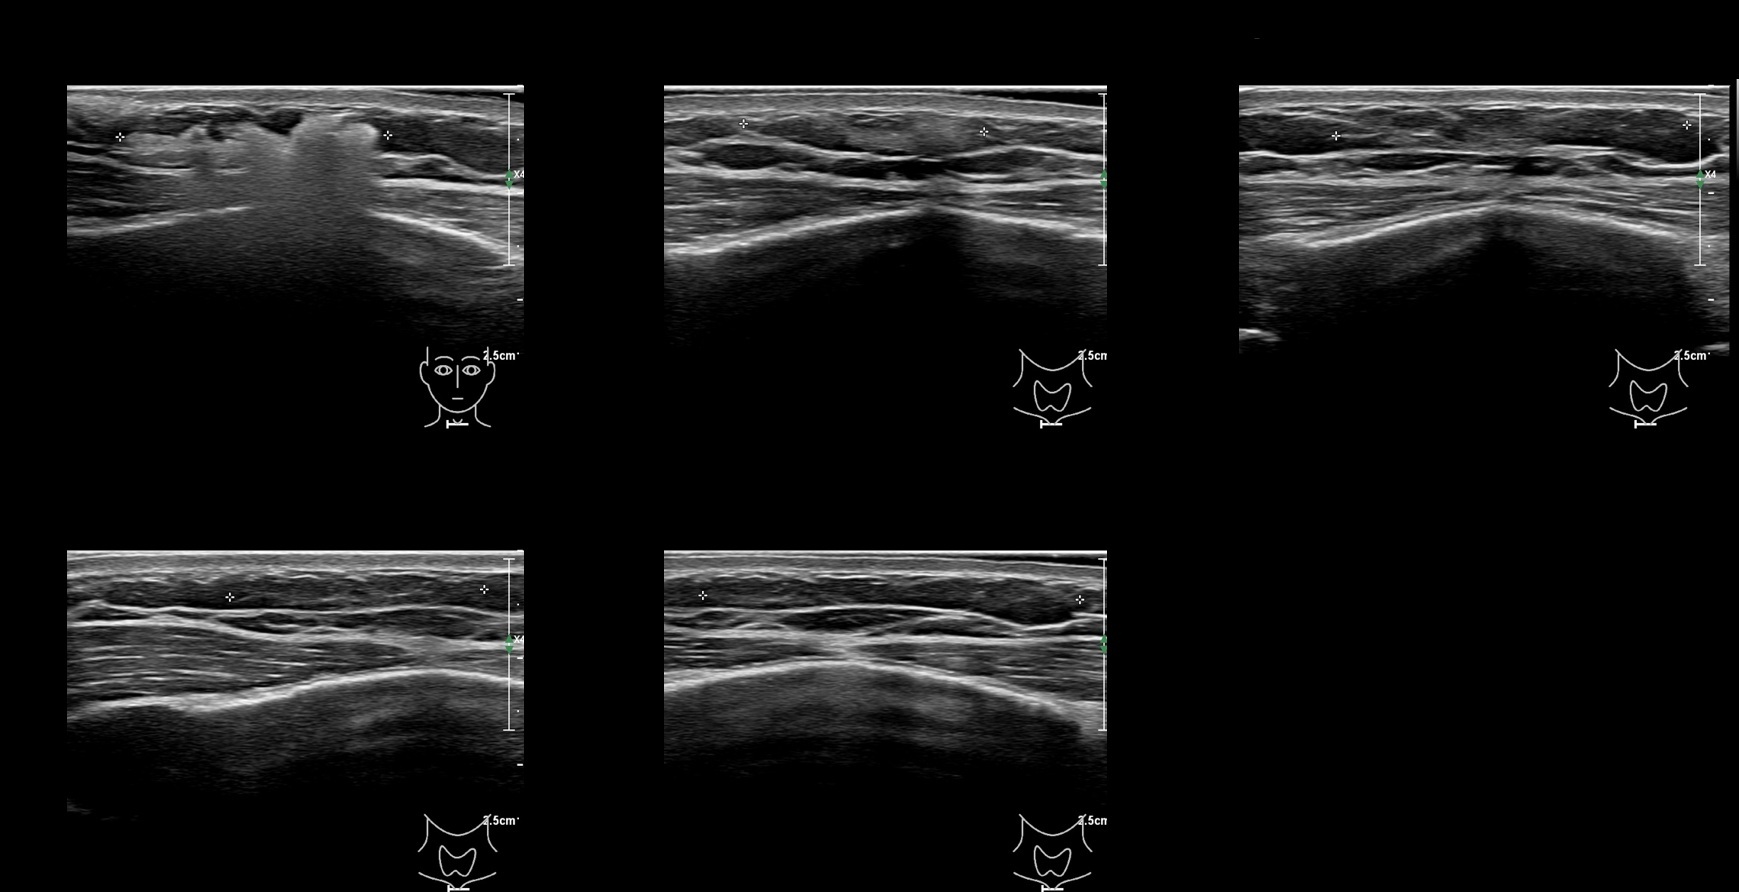

Filler library

CaHa 5a

caha 5b e

caha 60 b e

CaHa 60a

caha 61a

caha 61b e

caha 62a

caha 62b e

caha 63a

caha 63b e

CaHa 69a

CaHa 6a

caha 6b e

CaHa 70a

CaHa 7a

caha 7a e

caha 8a

caha 8b e

caha 9a

caha 9b e

caha0

caha69b e

caha70b e